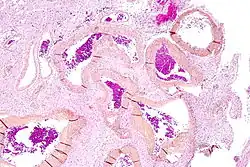

Micrograph of an arteriovenous malformation in the brain. HPS stain. | |